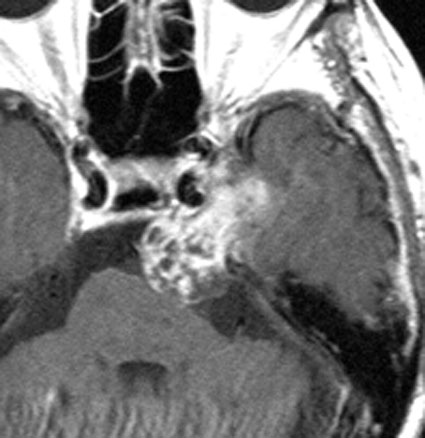

三叉神経鞘腫は,頭蓋底の孔(上眼窩裂,正円孔,卵円孔)から眼窩内や頭蓋底,鼻咽腔に伸びることがあります。CTで頭蓋底骨の孔の拡大があることで診断がつきます。bone erosionといって徐々に大きくなる腫瘍の特徴的な所見です。

左上顎癌と間違えそうなMRI画像です。CTでは左の正円孔(黄色の矢印)が辺縁が滑らかに拡大 erosion しているので三叉神経第2枝(上顎神経)の神経鞘腫の診断がつきます。